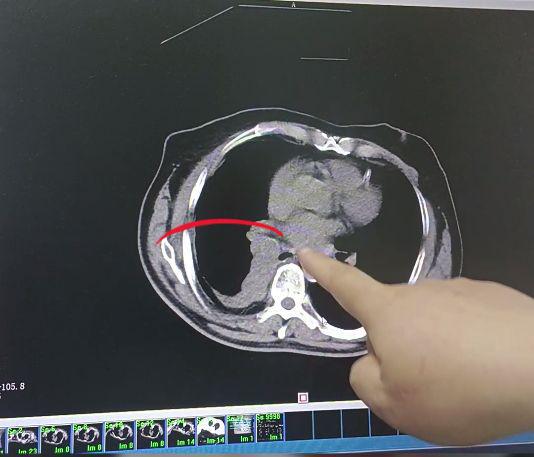

肺癌,在我国的发病率很高,而且因其治疗周期长、手段复杂,也被患者戏称为烧钱的癌症。作为一名肿瘤科医生,见过的患者很多,可以明确告诉大家,肺癌的治疗费用,受病程阶段、治疗方案及地域医疗差异影响显著。

另外,手术前一系列检查,如胸部 CT、肺功能测试、血液检查等,需花费几千元,用于评估身体状况,保障手术安全。术后住院观察、护理及康复治疗也需一定费用。

若需要影像及术前检查:术前通常需 CT、MRI、DSA(数字减影血管造影)等检查以精确定位肿瘤,费用约 3000 元 – 8000 元?;箍梢匝≡褚奖1ㄏ徊糠?。